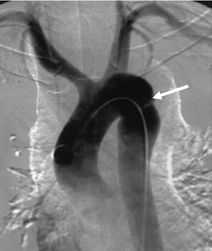

Аортография . Чувствительность и специфичность метода - 100%. Его главные неудобства – наличие высококвалифицированного персонала и трудоемкость.

Аортография: травматический разрыв аорты в области перешейка